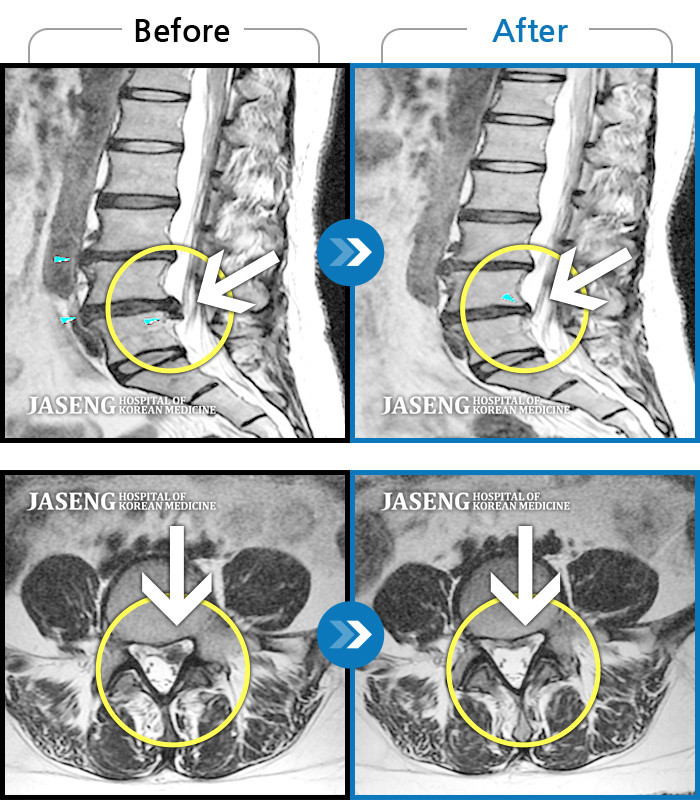

허리디스크

보라매 · 빈상은 원장

허리통증, 좌측 다리 바깥쪽으로 저림이 있어서 양말을 신기도 어려워요.

촬영시기

2022.12.12 ~ 2023.06.10

2023.11.24

조회수 182